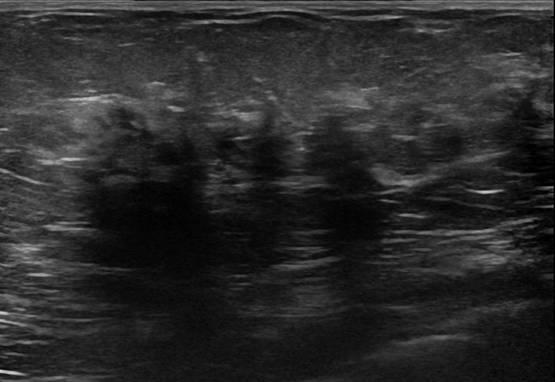

Ung thư vú

» Thông tin: Nữ giới – 58 tuổi.

» Lâm sàng: Khối tuyến vú.